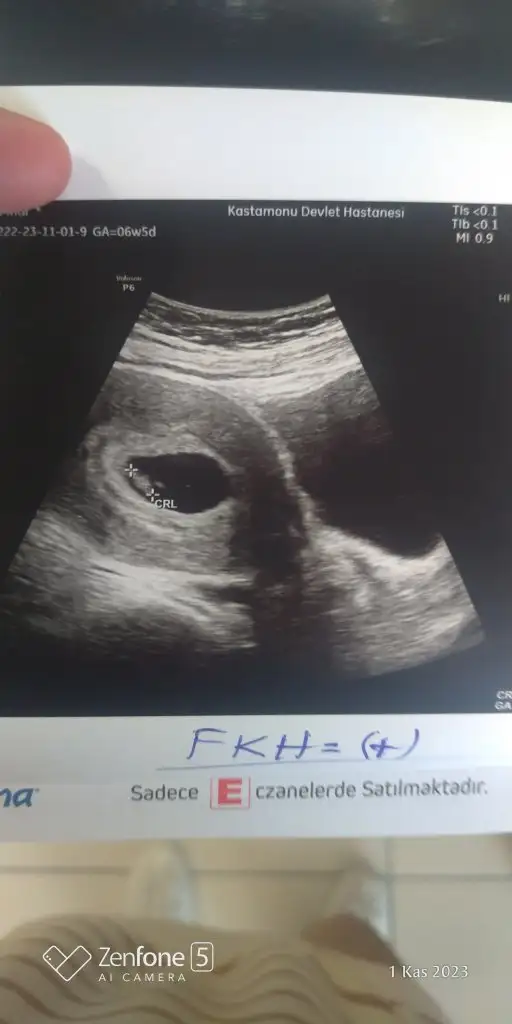

Banda bakarmisiniz 6+5 karından ultrasonKaç haftalık. Nuba göre paralel kız gözüküyor. Ancak ileri haftaysa o pipide olabilir

Bu haftada nub gözükmez. Ramzi diye pek tutmayan bi teori var .ona göre karındansa erkek.Banda bakarmisiniz 6+5 karından ultrason

Nub kaçıncı haftada anlaşılıyor ablaBu haftada nub gözükmez. Ramzi diye pek tutmayan bi teori var .ona göre karındansa erkek.

Görüntüyede bağlı 10 11 sanırım.Nub kaçıncı haftada anlaşılıyor abla